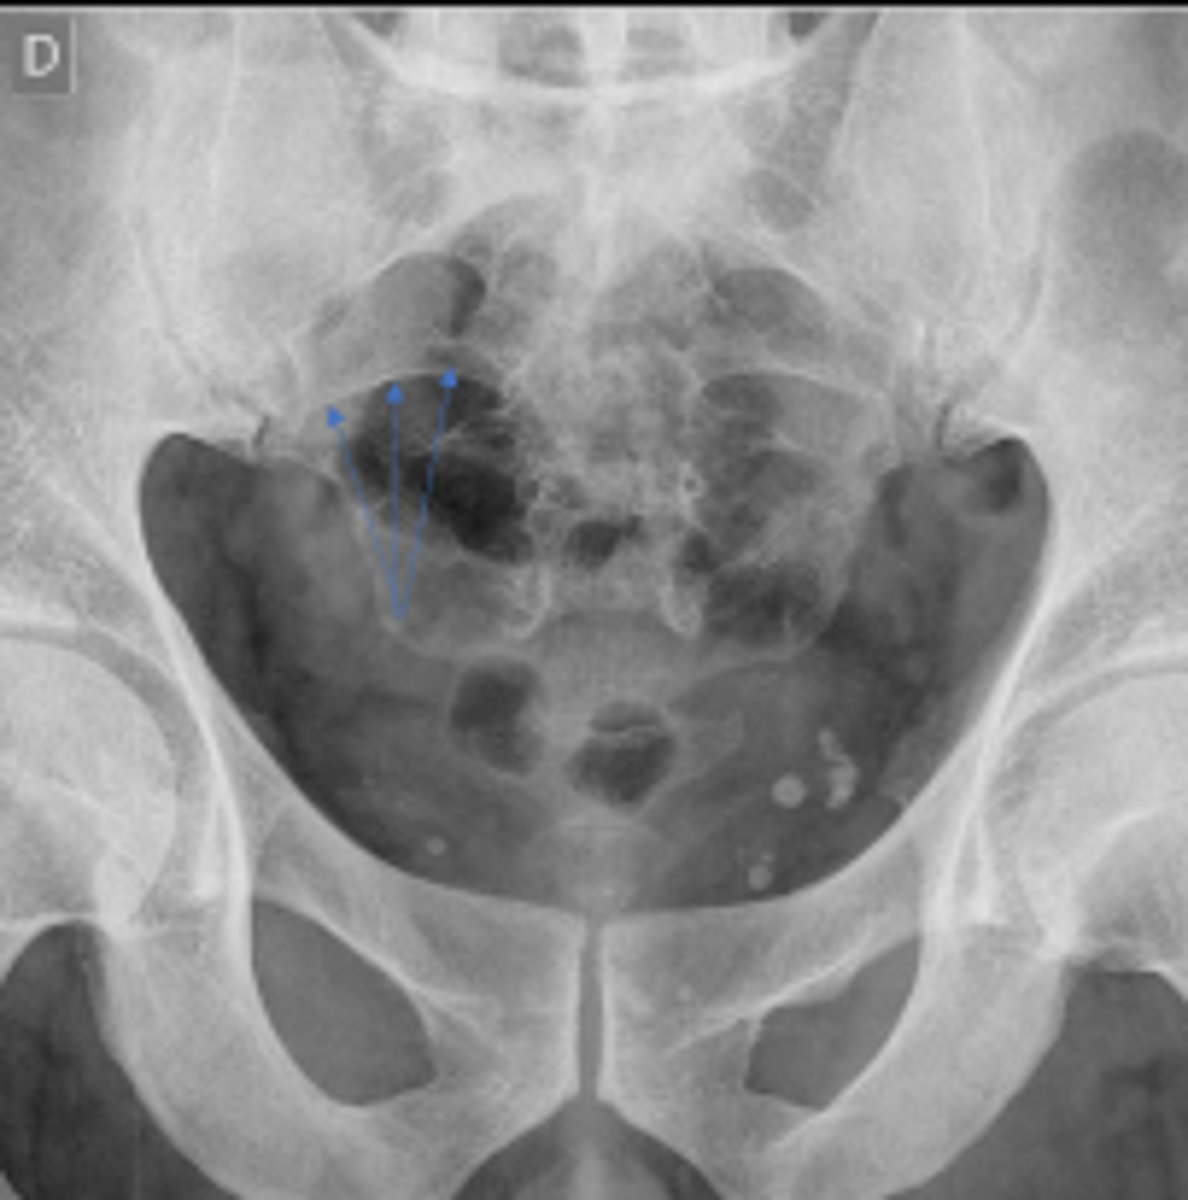

Bilateral frog leg view

What is the name of the radiographic view?

Phleboliths

What are the arrows pointing to?